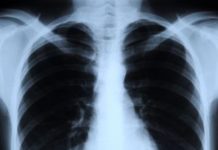

What Is an X-ray?

This longstanding form of medical imaging is still one of the most useful.An X-ray is a procedure that produces images o